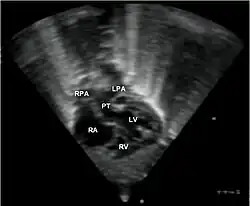

Echocardiogram in transposition of the great arteries. This subcostal view shows the left ventricle giving rise to a vessel that bifurcates, which is thus identified as the pulmonary artery.

Abbreviations: RA=right atrium, RV=right ventricle, LV=left ventricle, PT=pulmonary trunk, LPA and RPA=left and right pulmonary artery.